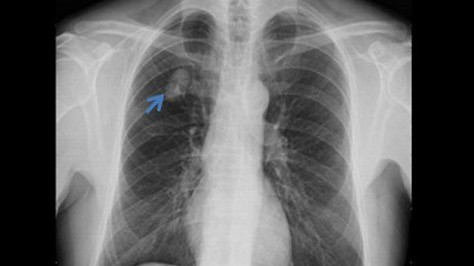

Người đàn ông phát hiện u phổi sau khi khám sức khỏe định kỳ

Bệnh ung thư -  01/02/2021

TS.BS Nguyễn Vũ Thiện, Khoa Giải phẫu bệnh, Bệnh viện Nhân dân 115 (TP.HCM) cho biết, bệnh viện vừa phẫu thuật cho nam bệnh nhân N.T.B (65 tuổi, ngụ...